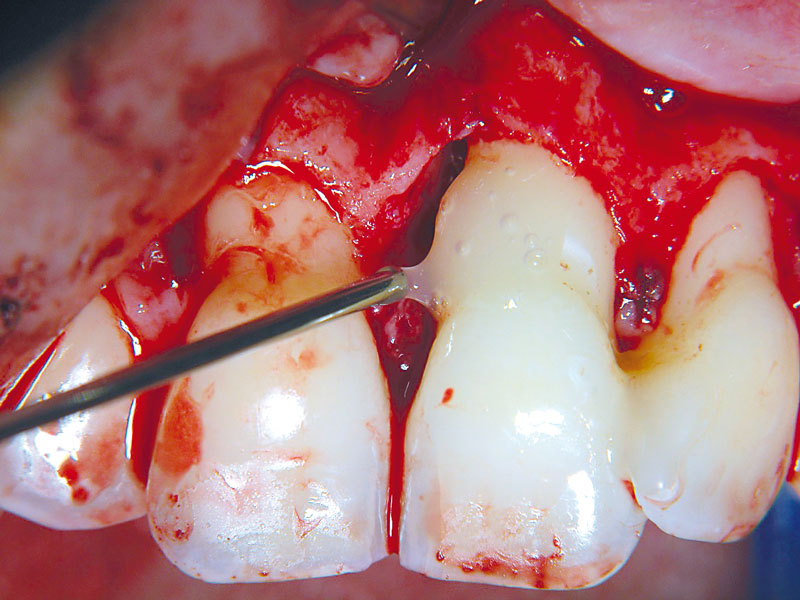

05/11 - Straumann® Emdogain® applied on the cleaned and pre-conditioned root surface.Non-contained intrabony defect treated using cerabone®, collprotect® membrane and Straumann® Emdogain® - Dr. T. Schwaar (2)